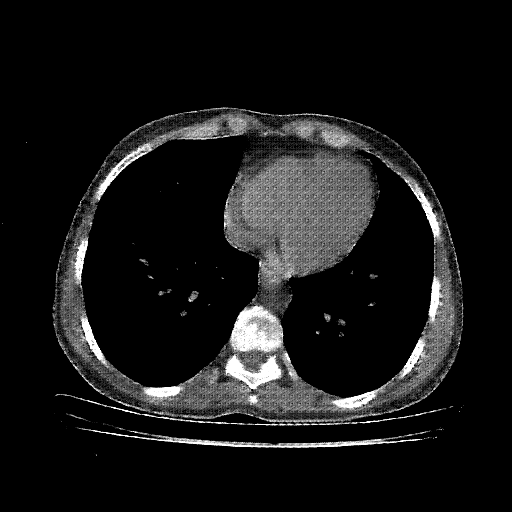

Generated VENOUS CT scan (A→B translation)

No window - Raw intensity values

Lung window (WL -600, WW 1500 β†’ Low βˆ’1350, High +150)

Mediastinum window (WL 40, WW 400 β†’ Low βˆ’160, High +240)